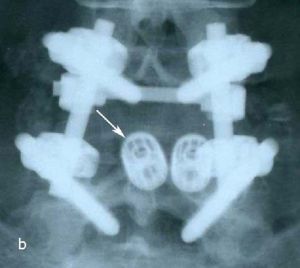

Рис. 2a,b. Рентгенограмма поясничного отдела позвоночника в боковой (а) и прямой (b) проекции после операции транспедикулярной фиксации L4-L5 позвонков. Стрелкой указаны 2 титановых цилиндрических кейджа.

Рис. 6a. Рентгенограмма поясничного отдела позвоночника в боковой (а) и прямой (b) проекции после операции транспедикулярной фиксации L4-L5 позвонков. Стрелкой указаны 2 титановых цилиндрических кейджа. Рис. 6b. Рентгенограмма поясничного отдела позвоночника в боковой (а) и прямой (b) проекции после операции транспедикулярной фиксации L4-L5 позвонков. Стрелкой указаны 2 титановых цилиндрических кейджа.